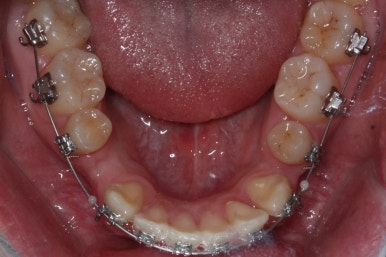

좁아져 있는 위턱뼈를 가로로 넓혀주기 위해서 악궁확장장치를 사용했습니다.

윗니는 선천결손으로 치아가 2개가 모자랐고 앞니도 거꾸로 물리는 상황이여서 아랫니도 균형있게 2개를 추가로 더 뽑았습니다.

악궁확장과 동반하여 부산구순구개열 키다리아저씨치과에서는 브라켓을 부착하여 가지런하게 하는 작업을 시작하였습니다.

위아랫니가 각각 가지런해지고 있는 것을 볼 수 있습니다.